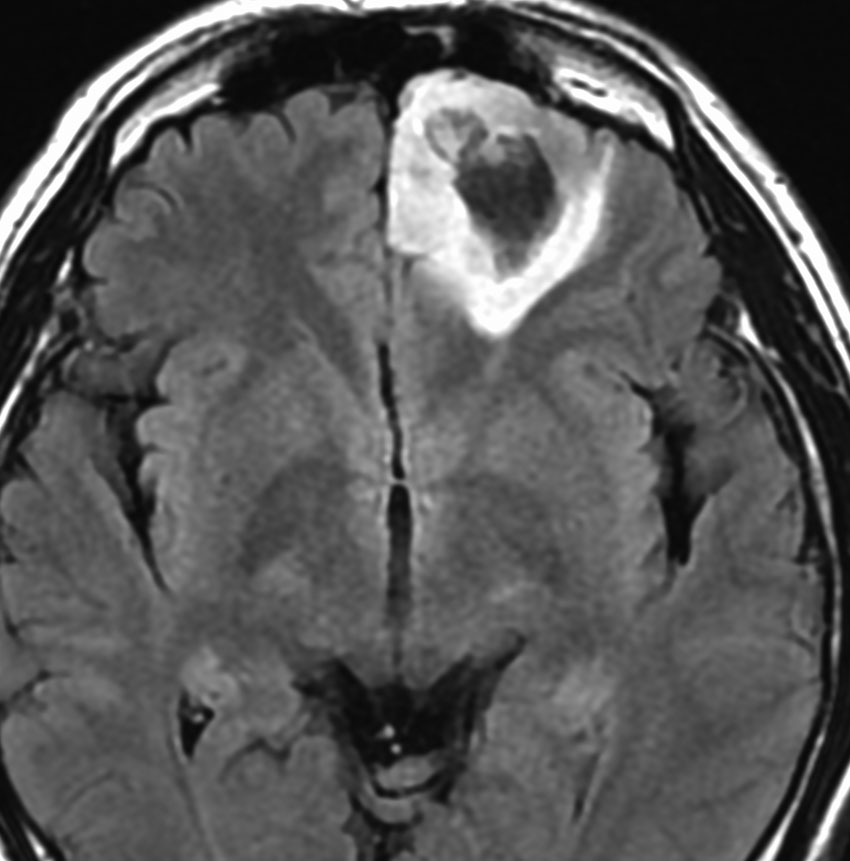

30代の患者さんです。起立性低血圧や呼吸苦,右片麻痺と多彩な脳神経症状で発症しました。

左はT2強調画像で,延髄を中心とするびまん性グリオーマの所見です。右はがドリニウム増強像で,一部が増強されて白く見えています。

50.6Gy/28fr, TMZ 24コースの治療をした4年後のMRIです。腫瘍は縮小して固まったようにみえ,症状も落ち着いて自宅で暮らせてました。

しかしこの後に,激しい腫瘍再燃があり制御できませんでした。